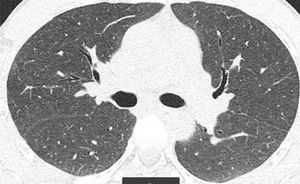

Presentamos el caso de un varón de 41 años, exfumador de 10 paquetes/año, pulidor de piedras preciosas en un taller de joyería desde hace 20 años, para lo cual utiliza material con una aleación de Be. Residente en entorno urbano, sin exposición a otras sustancias inhaladas. Fue remitido a neumología por referir disnea grado I (MRCm) en los últimos 4 meses, sin ningún síntoma respiratorio previo. El estudio de función pulmonar mostró FVC: 4.060ml (79%); FEV1: 3.330ml (81%); FEV1/FVC: 82%; RV: 2.430ml (116%); TLC: 6.570ml (89%); DLCO: 26,7ml/min/mmHg (79%) y KCO: 4,84ml/min/mmHg/l (91%). La tomografía computarizada de tórax permitió identificar un tenue patrón nodular de características centroacinares con densidad en vidrio deslustrado, de bordes mal definidos, bilateral y difuso, con un ligero predominio en lóbulos superiores. No se observó aumento de tamaño de ganglios hiliares ni mediastínicos (fig. 1). La biopsia transbronquial puso de manifiesto un tejido pulmonar con patrón preservado en zonas, con tabiques inter-alveolares finos, sin depósitos y que focalmente mostraba una infiltración inflamatoria con acúmulo de células epitelioides, bien delimitado, sin necrosis y con células multinucleadas, sin material extraño en su interior. El recuento celular del lavado broncoalveolar mostró el siguiente resultado: linfocitos 90%, neutrófilos 1%, macrófagos 8%, eosinófilos 0% y un cociente de linfocitos CD4/CD8 de 4. Se realizaron estudios microbiológicos completos del aspirado bronquial con resultados negativos.